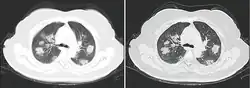

From the CT scans of COVID-19 infected lungs, white patches were observed containing fluid known as ground-glass opacity (GGO) or simply ground glass.[130] This tended to correlate with the clear jelly liquid found in lung autopsies of people who died of COVID-19. One possibility addressed in medical research is that hyuralonic acid (HA) could be the leading factor for this observation of the clear jelly liquid found in the lungs, in what could be hyuralonic storm, in conjunction with cytokine storm.[131]

Imaging

Chest CT scans may be helpful to diagnose COVID‑19 in individuals with a high clinical suspicion of infection but are not recommended for routine screening.[175][187] Bilateral multilobar ground-glass opacities with a peripheral, asymmetric, and posterior distribution are common in early infection.[175][188] Subpleural dominance, crazy paving (lobular septal thickening with variable alveolar filling), and consolidation may appear as the disease progresses.[175][189] Characteristic imaging features on chest radiographs and computed tomography (CT) of people who are symptomatic include asymmetric peripheral ground-glass opacities without pleural effusions.[190]

Many groups have created COVID‑19 datasets that include imagery such as the Italian Radiological Society which has compiled an international online database of imaging findings for confirmed cases.[191] Due to overlap with other infections such as adenovirus, imaging without confirmation by rRT-PCR is of limited specificity in identifying COVID‑19.[190] A large study in China compared chest CT results to PCR and demonstrated that though imaging is less specific for the infection, it is faster and more sensitive.[174]